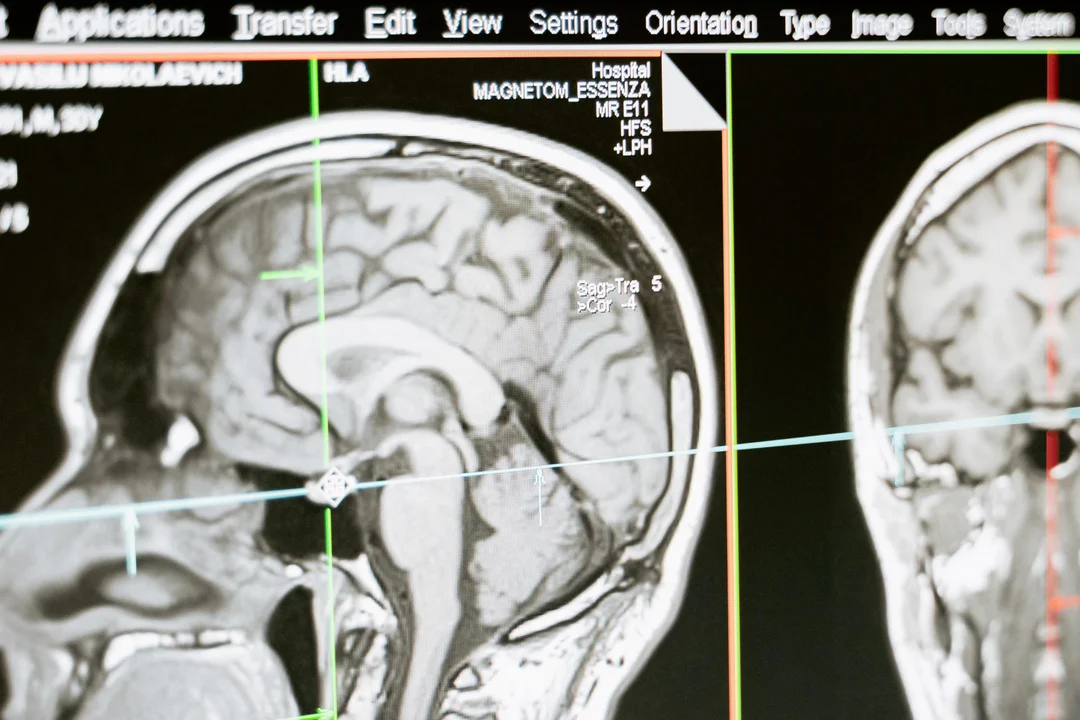

Gwałtownie rośnie liczba niedokrwiennych udarów mózgu. Będzie ich jeszcze więcej. Sprawdź, czy jesteś w grupie ryzyka - Zdjęcie główne

Średnio co 6,5 minuty ktoś w Polsce doznaje udaru mózgu. To pierwsza przyczyna trwałej niepełnosprawności wśród dorosłych Polaków. | foto pexels